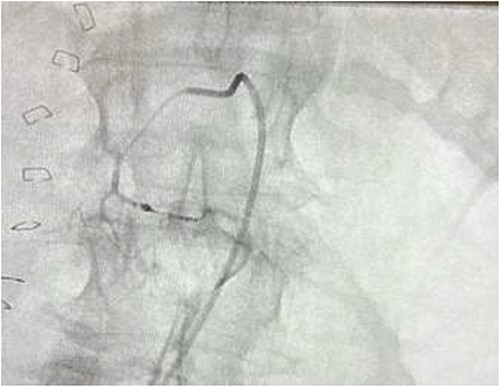

CTA demonstrated angiodysplasia in the duodenal diverticulum at the duodenojejunal junction with associated contrast blush (Figs 1 and 2). The urgent opinion of an interventional radiologist was sought in a tertiary centre. The patient was accepted for urgent embolization in an attempt to stabilize the patient. The patient required an intra-hospital transfer overnight.

The on-call interventional radiology team performed a successful embolization. A 6-French Sheath was passed through the left common femoral artery, and a 5-French Sim-1 catheter was advanced into the coeliac and common hepatic artery. A 2.4 French Direxon microcatheter was advanced into a branch of the superior mesenteric artery at the site of bleeding. Successful coil embolization with a 2 mm × 2 mm concerto micro coil was performed. A satisfactory angiographic result with DYNA-CT, also known as modern C-arm CT or cone-beam CTA, showed no extravasation.